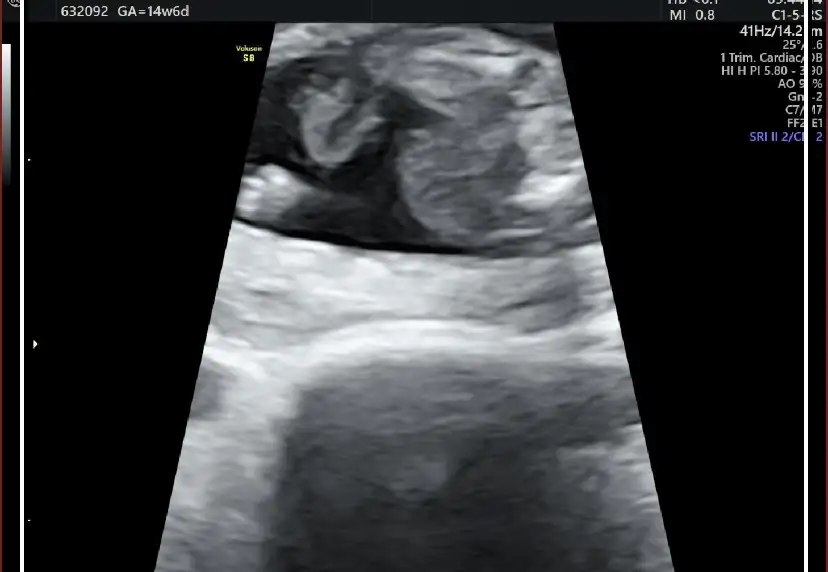

nerden başlasam bilemiyorum o kadar aklım karışıkki ne yapacağımı bilemiyorum lütfen fikirlerinizi yazın. son adet tarifime göre 15 haftalık hamileyim bebeğin kalp atışını duyana kadar günü tutuyordu. sonra 12 haftalıkken kontrole gittim gününden sapmış hastalıklı bir bebek olma ihtimalinin olduğunu söyledi doktor başka doktorada göründüm oda perinatolojiye yönlemdirdi.2 gün önce gittim.15 haftalık gebeliğim,16+5 olarak gözüküyordu. doktor o kadar şey saydıki bebeğin yaşama ihtimali yok dedim ama doktor doğabileceğini ama doğsa bile yaşama ihtimalinin çok düşük olduğunu söyledi.ense kalınlığı ve burun kemiğinin küçük oluşundan down sendromlu olduğunu. iki bacağınında eğri ve kısa olduğunu. iki böbreğininde çalışamaz durumda olduğu için vücudunun su topladığını böbreklerinin iflas ettiğini ve karnında oluşan fıtıktan dolayı karaciğer ve bağırsaklarının dışarda olduğunu söyledi. böylelikle dünyam başıma yıkıldı sonlandırmak gerektiğini ve bunun günah olmadığını söyledi doktor. öyle bir durumdaydımki sonlandırmak bile benim için umuttu ama diyanet danışma hattını aradım bana bebek karnımda olduğu sürece bana zarar verme riski bulunmadıkça günah olduğunu söyledi. bebeğin kalbinde bir sıkıntı yok yaşar diye korkar mı bir anne kendimi çok kötü hissediyorum ölmesini istediğim için. ama doktor yaşarsada zihinende bedenende ileri derece özürlü olacağını tuvalete bile gidemeyeceğini söyledi hem onun için hem bizim için çok zor bir süreç olduğunu yaşlarımızında daha çok genç olduğunu sonlandırmak gerektiğini söyledi.sonlandırırsam ilerde daha kötüsü gelir başıma diye korkuyorum zaten bugüne kadar ne konuşursam başıma bela olarak tekrar karşıma çıkıyor elim kolum bağlı bir durumda amniyosentez testimin sonucunu bekliyorum.aşağı bebeğin bir kaç görüntüsünü bırakacam ben pek bir şey anlamasamda belki siz anlarsınız.